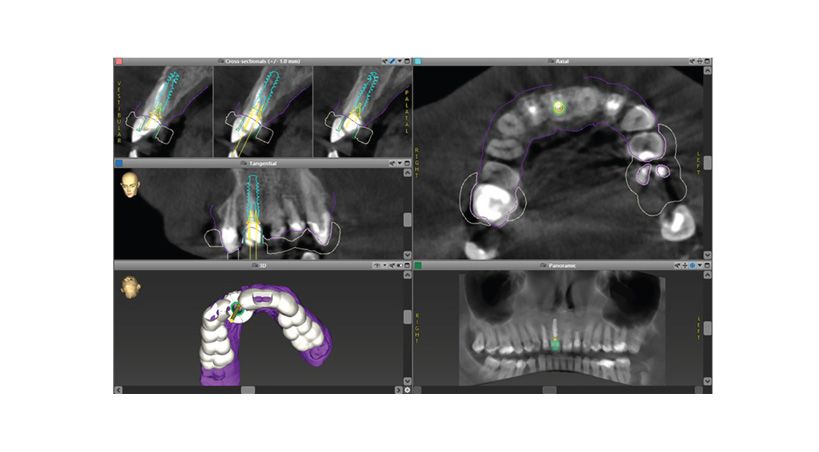

La técnica Socket-Shield

Planificación digital, cirugía guiada y carga inmediata de implantes: seguimiento de 2 años